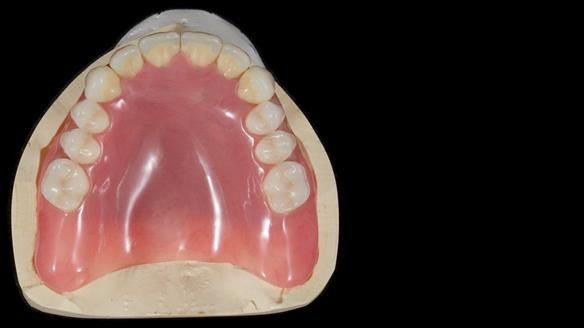

We provided her with an immediate upper denture (Mk 1), followed by a definitive metal-based upper denture (Mk 2). A lower removable partial denture was discussed, to be made only if needed once the upper treatment was complete. However, at review, this wasn’t necessary — Adnana had excellent neuromuscular control and function, even with a shortened dental arch (SDA).

Rowan, Sam Hesketh and Chris Hesketh provided the stunning technical work. I am very lucky to have them.